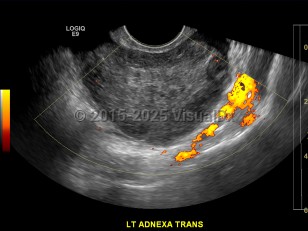

Ovarian torsion is an acute condition that can be a true gynecologic emergency. It occurs when an ovary twists on the adjacent infundibulopelvic ligament, causing disruption of blood supply to the ovary and in effect creating a tourniquet. Torsion accounts for 2.7% of all gynecologic emergencies. It is more common in women 20-30 years of age, but it can occur at any age from early childhood (rare) to after menopause. Ovarian torsion more commonly occurs on the right side.

Risk factors include ovarian cyst with size greater than 4-6 cm or with solid components, history of prior torsion, pregnancy, and history of pelvic surgery. Patients may not have had a history of ovarian cysts prior.